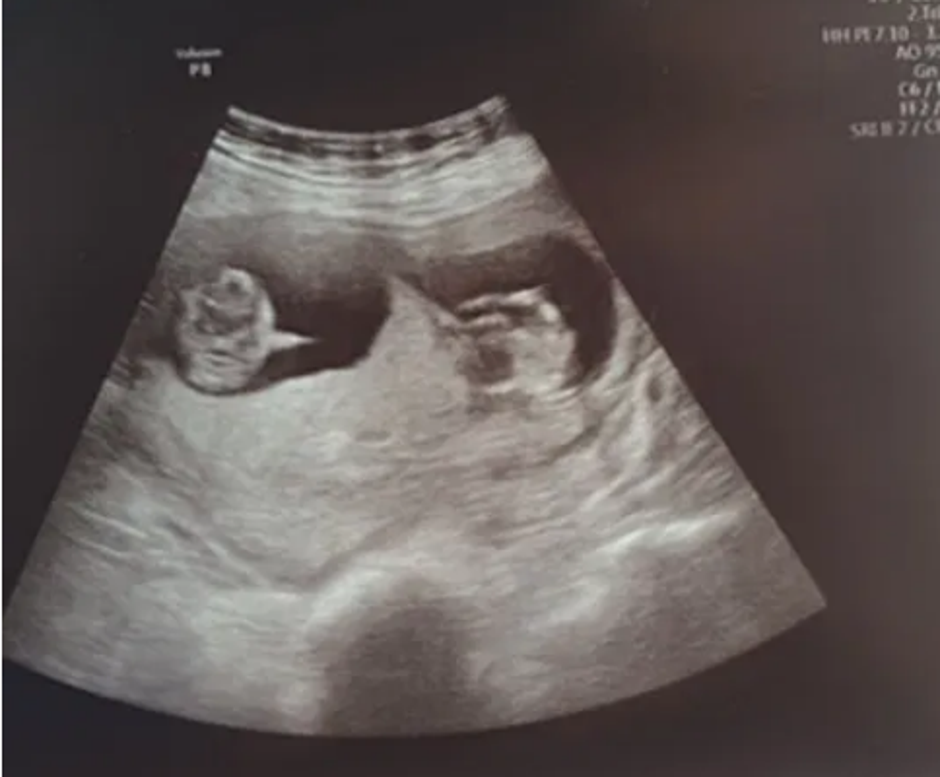

Nakon deset dana u induciranoj komi Danielle se probudila i pitala je li njena beba dobro, a liječnici su otkrili da ne nosi jednu, već dvije. Ovaj težak period ipak će pamtiti po nečem predivnom.

Nakon deset dana u komi Danielle se probudila, a liječnici su joj rekli kako čeka blizance. "Probudila sam se jako zbunjena, ali kada sam došla k sebi bila sam neizmjerno zahvalna. Nisam mogla vjerovati kada su mi rekli da nosim blizance. Bila je to višnja na vrhu torte, znala sam da sam pobijedila koronavirus i da čekam dvije bebe. Barem ćemo se sjećati nečeg dobrog iz ovog perioda."

"Kada je došla k sebi nazvala me i rekla da su obje bebe dobro, a ja sam pomislio 'obje?!' Mislio sam da je možda zbunjena još od svega, ali bio sam sretan kada sam shvatio da nosi blizance", zaključio je Bryan koji je pokrenuo udrugu koja skuplja novac za medicinsko osoblje u Belfast Nightingale bolnici nakon što su spasili život njegovoj supruzi i dvoje djece na putu.